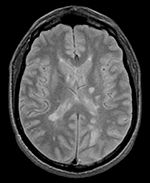

Lesion change visualization in 3D Lesion change via subtraction imaging of co-registered PD